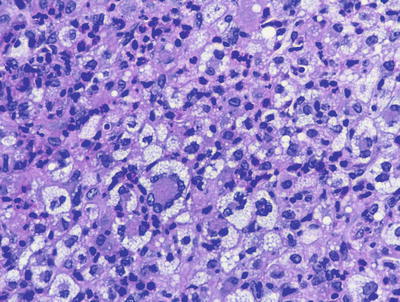

The cutaneous lesions in Rosai-Dorfman disease are histologically quite similar to changes described in the more common lymph node-based sinus histiocytosis with massive lymphadenopathy. A dense infiltrate of inflammatory cells fills much of the dermis with no tendency for invasion of the epidermis or cutaneous appendages [55, 56] (Figs. 22.16 and 22.17). Admixed with sheets of histiocytes are lymphocytes, neutrophils, plasma cells, and occasional eosinophils [57]. The histiocytes resemble those seen in lymph node sinuses and demonstrate emperipolesis, in which histiocytes engulf other inflammatory cells [58, 59]. While this finding is not pathognomic for the disease, it is a very characteristic finding in this entity, and is usually readily apparent on H&E staining. Plasma cells are often found rimming blood vessels within the midst of the lesions. Thick-walled vessels and lymphoid nodules have been described at the periphery of lesions [55].

Fig. 22.16

The dermis is filled with large histiocytes admixed with a dense inflammatory infiltrate. The infiltrate may extend into the subcutis in sinus histiocytosis with massive lymphadenopathy

Fig. 22.17

Large histiocytes may demonstrate emperipolesis, and may be surrounded by a dense collection of lymphocytes with occasional plasma cells and eosinophils in sinus histiocytosis with massive lymphadenopathy. Endothelial cells in dermal vessels are edematous and resemble small granulomas